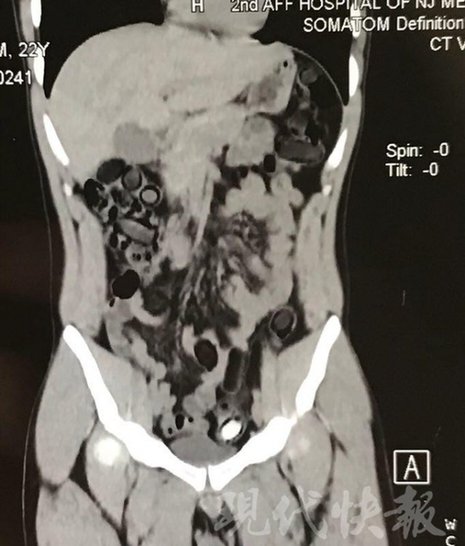

運毒小伙:希望被判處死刑

由于毒品在體內一旦泄露有可能致命,警方第一時間將阿永帶到醫(yī)院進行檢查。CT 掃描的結果顯示,阿永體內布滿了密密麻麻的白色圓柱狀固體,就像一粒粒的蠶蛹。在南京市公安局鼓樓分局二板橋派出所,阿永分四次排出了毒品,毛重369.99克。經(jīng)訊問,阿永交代了自己全部的犯罪事實。目前,阿永已被刑事拘留。